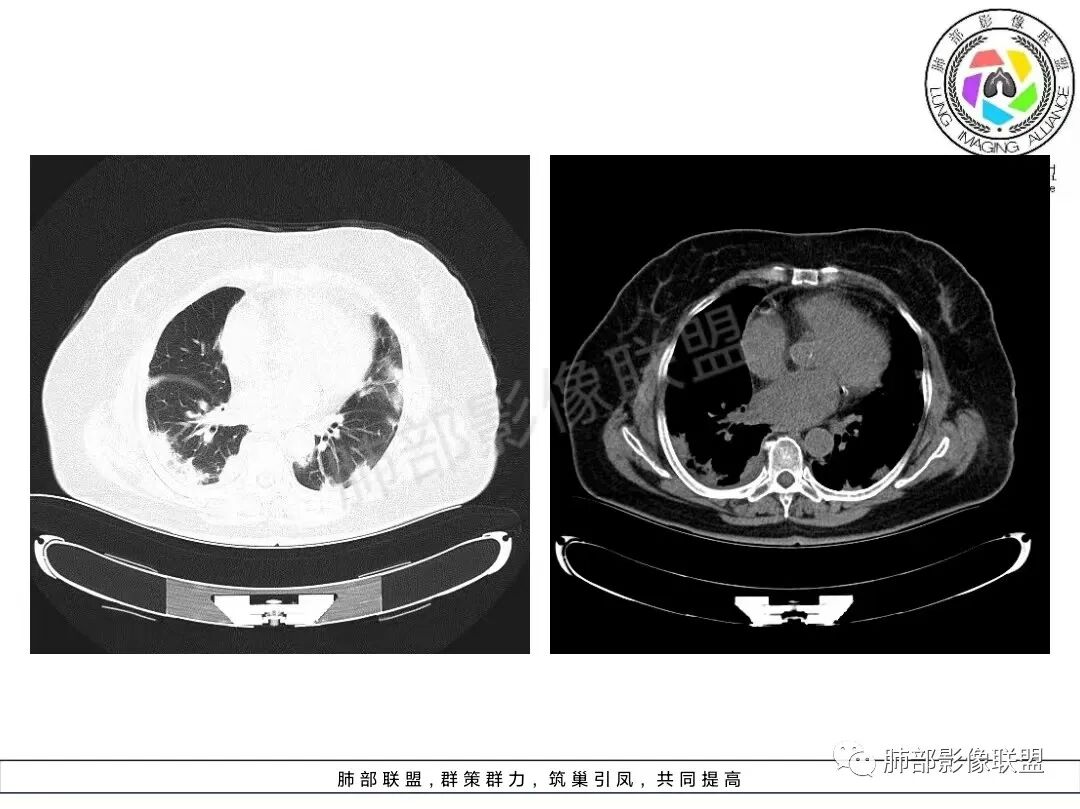

1、临床特点:70岁女性,务农。咳嗽咳痰伴气急20天。症状逐渐加重。有高血压病史。入院查体:体温37.5℃,急性面容。白细胞、CRP、红细胞沉降率升高。血糖高,CEA升高、余肿瘤标志物正常。ANCA检查阴性。血培养阴性,支气管灌洗液培养、真菌检测、抗酸杆菌均阴性。

2、影像特点:双肺胸膜下为主、多发斑片影、结节样实变影及磨玻璃样密度影,大部分病灶边缘平直、边界清,磨玻璃密度病灶内可见细网格影,部分病灶内可见支气管扩张表现,部分支气管直达远端,部分中断于病灶中部。部分病灶有侧向融合趋势。

3、病例小结:老年女性,咳嗽咳痰伴气急逐渐加重,入院后有低热。部分炎性指标升高,肺部片影,可以符合感染性病变,但是血培养、支气管灌洗液培养等检查无阳性表现。但仍影警惕隐球菌感染,患者临床表现相对轻微,胸膜下病灶,磨玻璃影等。

影像上双肺多发磨玻璃影及实行密度影,对称分布趋势,op样改变,结缔组织相关性疾病需要排除。临床上可进一步查皮肌炎相关指标、仔细进行体格检查看看患者皮肤等情况。